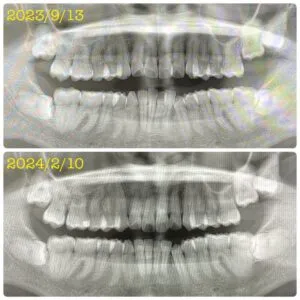

全体のレントゲンを撮ってみたところ、矯正前とは明らかに変わっている歯並び🦷✨

まだまだ矯正途中ではありますが、「こんなに変化していたんだ!」と驚きました😳